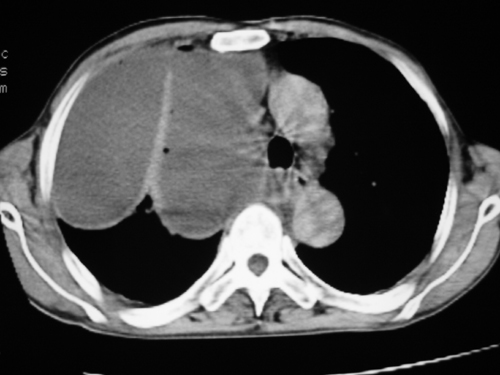

以下是引用zsl6918在2008-4-29 9:15:00的发言:[br]右侧包裹性积液穿刺术后改变,肺内多发结节不除外转移可能。建议查胸水,问病史。